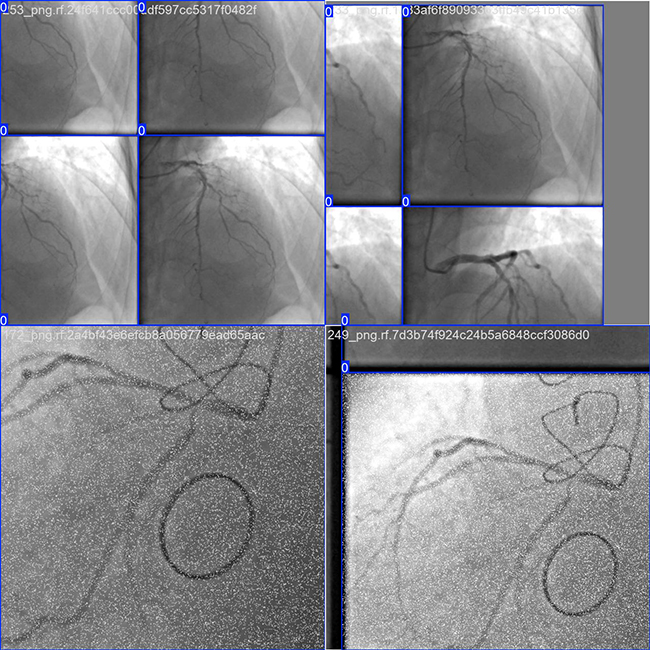

目标检测训练数据可视化

目标检测训练过程中,模型对数据的可视化结果,主要展示了多个类别目标的检测边框和类别标注情况。整体检测表现较好,但可以通过优化标注和模型训练进一步提升精度和鲁棒性。